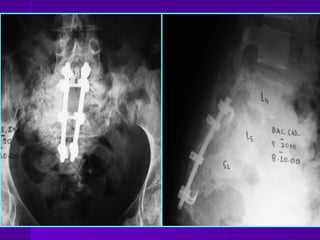

PERCUTANEOUS ILIOSACRAL SCREWFIXATION • For unilateral sacral fractures zone I or zone II • Under fluoroscopic control the reduction is obtained and held by iliac screws (cannulated)

OPEN REDUCTION ANDINTERNAL FIXATION